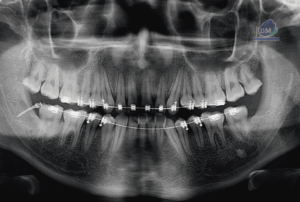

Paciente masculino de 55 años, es referido al Instituto de Diagnóstico Maxilofacial – IDM (Sede Surco) para planificación de implantes dentales. Radiografia Panorámica En la